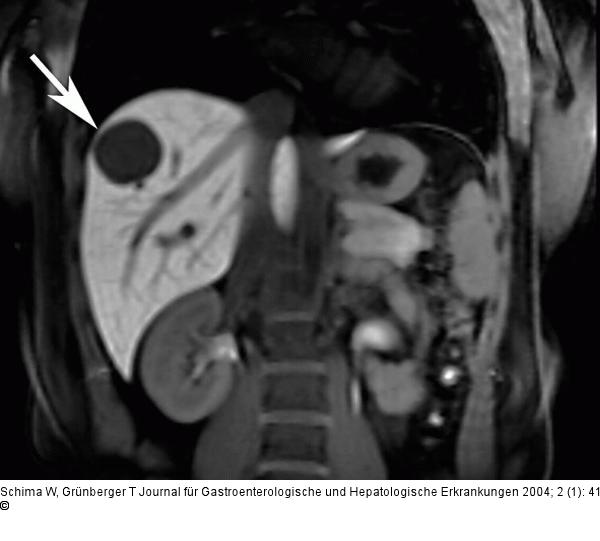

Aktuelle Bilder: Echinokokkus der Leber

Abbildung 1: Echinokokkus - Leber